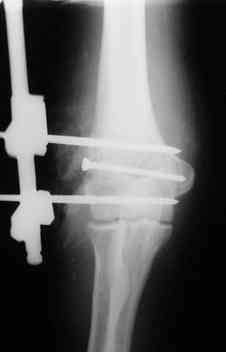

Отправитель: Алексей Минервин 12 Октябрь 2006, 01:40

Уважаемые коллеги. Внешний вид конечности через 5 недель после травмы. Рана гранулирует, отделяемое скудное. Прошу строго не судить за внешний вид АВФ: ну нет пока у нас параллельных зажимов (приходиться выкручиваться).

С уважением, А.Минервин.

через 5 недель.JPG